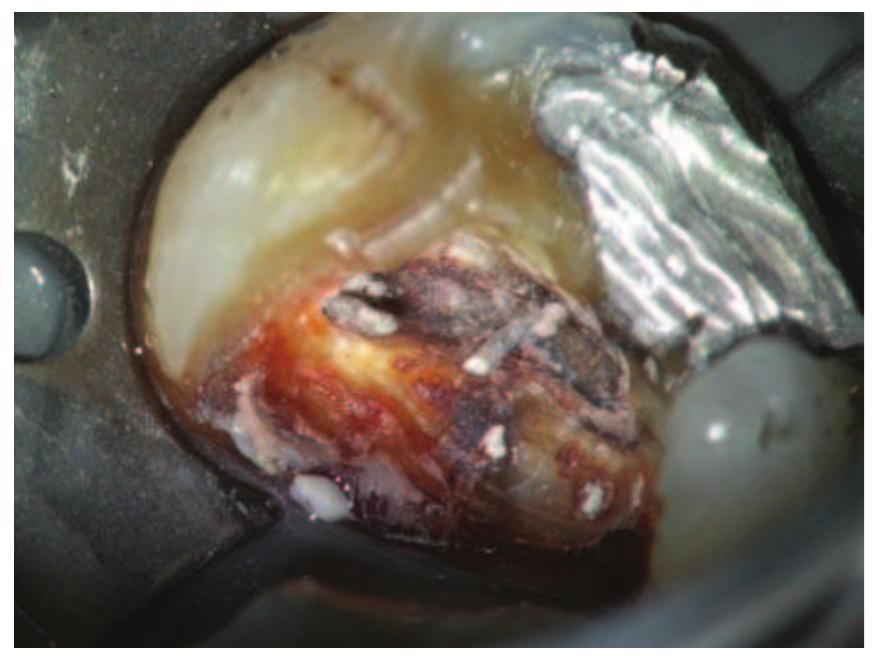

- There is little root filling material present and the root canal would undoubtedly be infected.